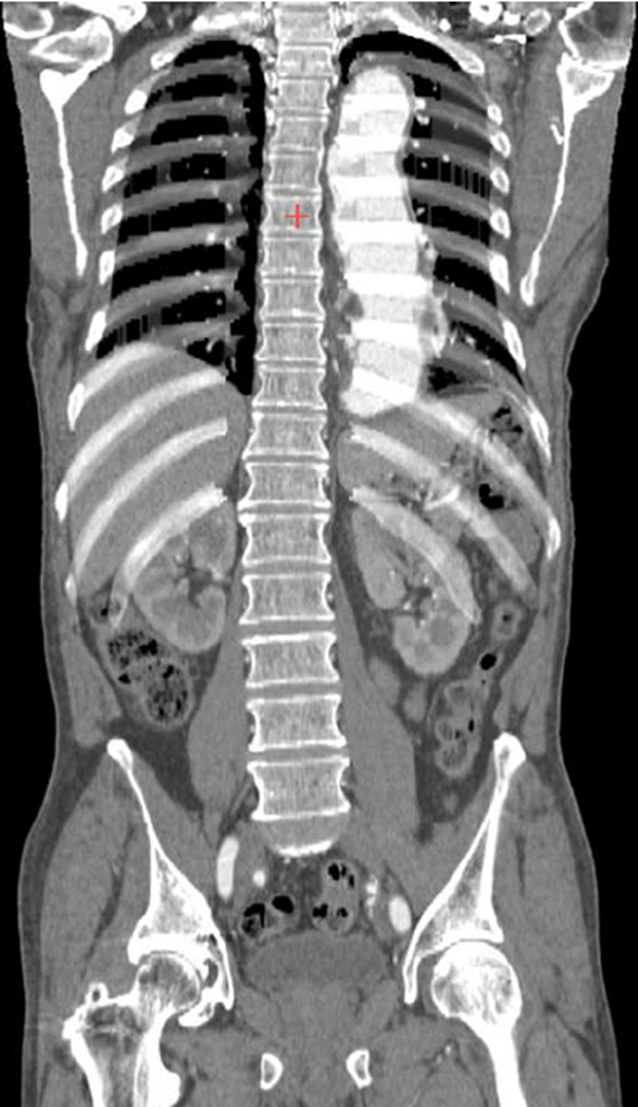

What view is this

sagittal MRI

coronal